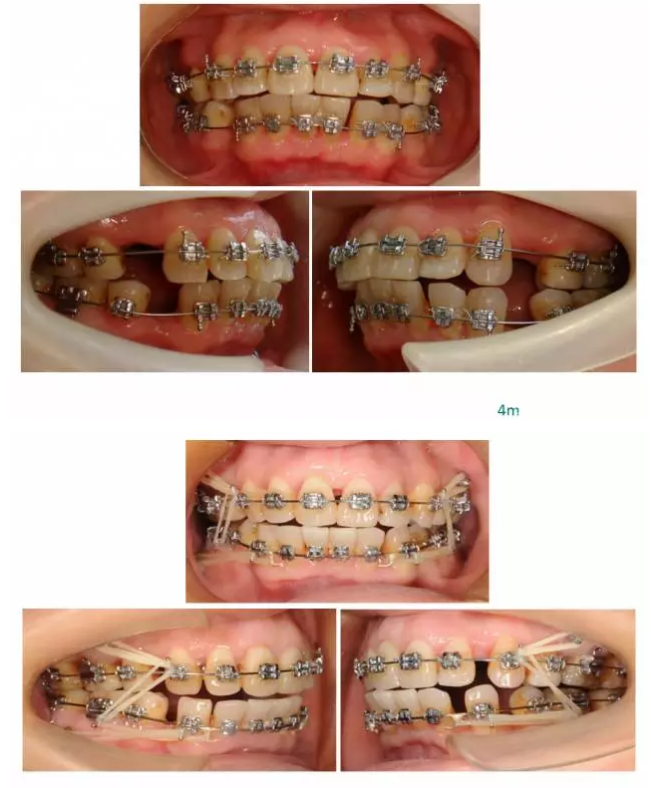

【原創(chuàng)博客】這樣的代償矯治大家滿(mǎn)意嗎?(重度骨性二類(lèi))——侯志明

轉(zhuǎn):侯志明 愛(ài)齒-KQ88口腔醫(yī)學(xué)